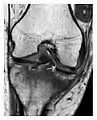

High-energy trauma fractures

Occult osseous injuries may result from a direct blow to the bone by compressive forces of adjacent bones against one another or by traction forces during an avulsion injury. Lesions in the tibial plateau, hip, ankle, and wrist are often missed. In a tibial plateau fracture, any disruption of the posterior and anterior cortical rims of the plateau should be sought. Impaction of subchondral bone will appear as an increased sclerosis of the subchondral bone (Figure 1). In the hip, posterior acetabular fractures also present subtle radiographic findings. The acetabular lines should then be carefully examined keeping in mind that the posterior rim, which is harder to see on X-rays, is more frequently fractured than the anterior rim (Figure 2). In the wrist, detection of carpal bone fractures is often challenging, with up to 18% of scaphoid fractures radiographically occult. Carpal fractures, especially the scaphoid, are associated with the risk of avascular necrosis. In apparently normal wrist radiographs from symptomatic patients, if there is history of a fall on an outstretched hand with pain in the anatomic snuffbox, suggesting scaphoid injury, the initial examination with posteroanterior, lateral, and pronation oblique views must be complemented by other specific views such as supination oblique and the "scaphoid" view A careful examination of cortices for evidence of discontinuity or offset and cancellous bone for lucency is necessary (Figure 3).[1]

a

b

c

Figure 1: A 56-year-old woman presenting with left knee pain after a fall. (a) Initial anteroposterior radiograph was considered normal, however, subtle cortical disruption of the anterior rim of the medial tibial plateau, medial to the tibial spine, is noted (arrow). (b) Coronal T1-weighted MRI confirms the cortical disruption (arrow) and shows extensive fracture through the proximal tibia. (c) Coronal proton density-weighted image with fat saturation shows extensive edema in the subchondral bone. Note also hypersignal adjacent to the medial collateral ligament corresponding to a grade I sprain (arrowheads).[1]